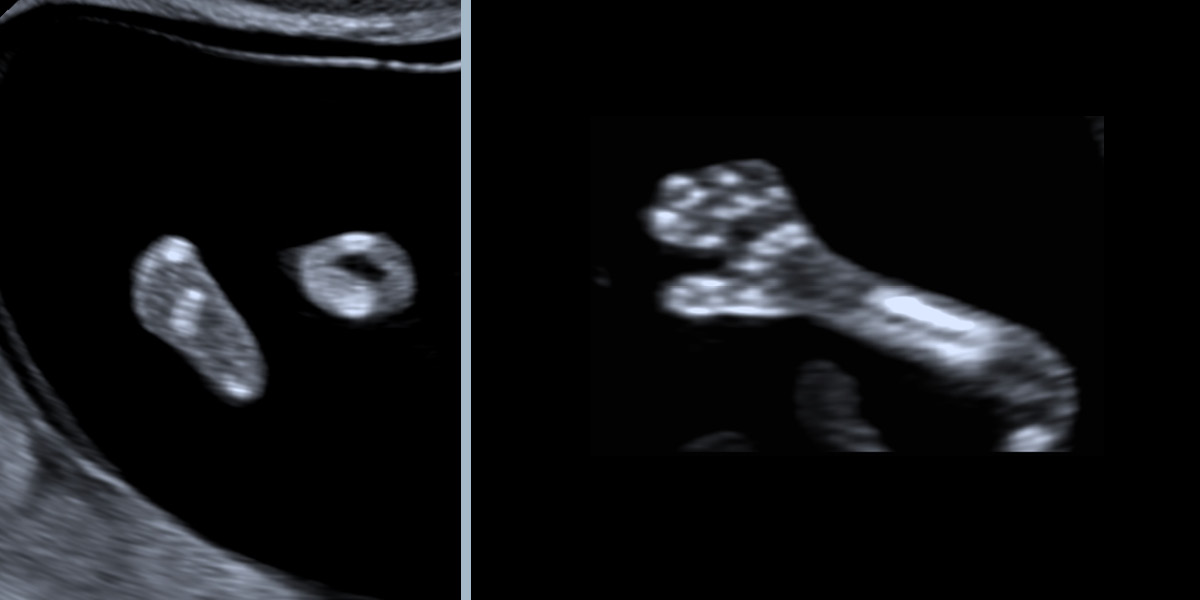

Auch Arme und Beine mit Händen und Füßen lassen sich bereits untersuchen.